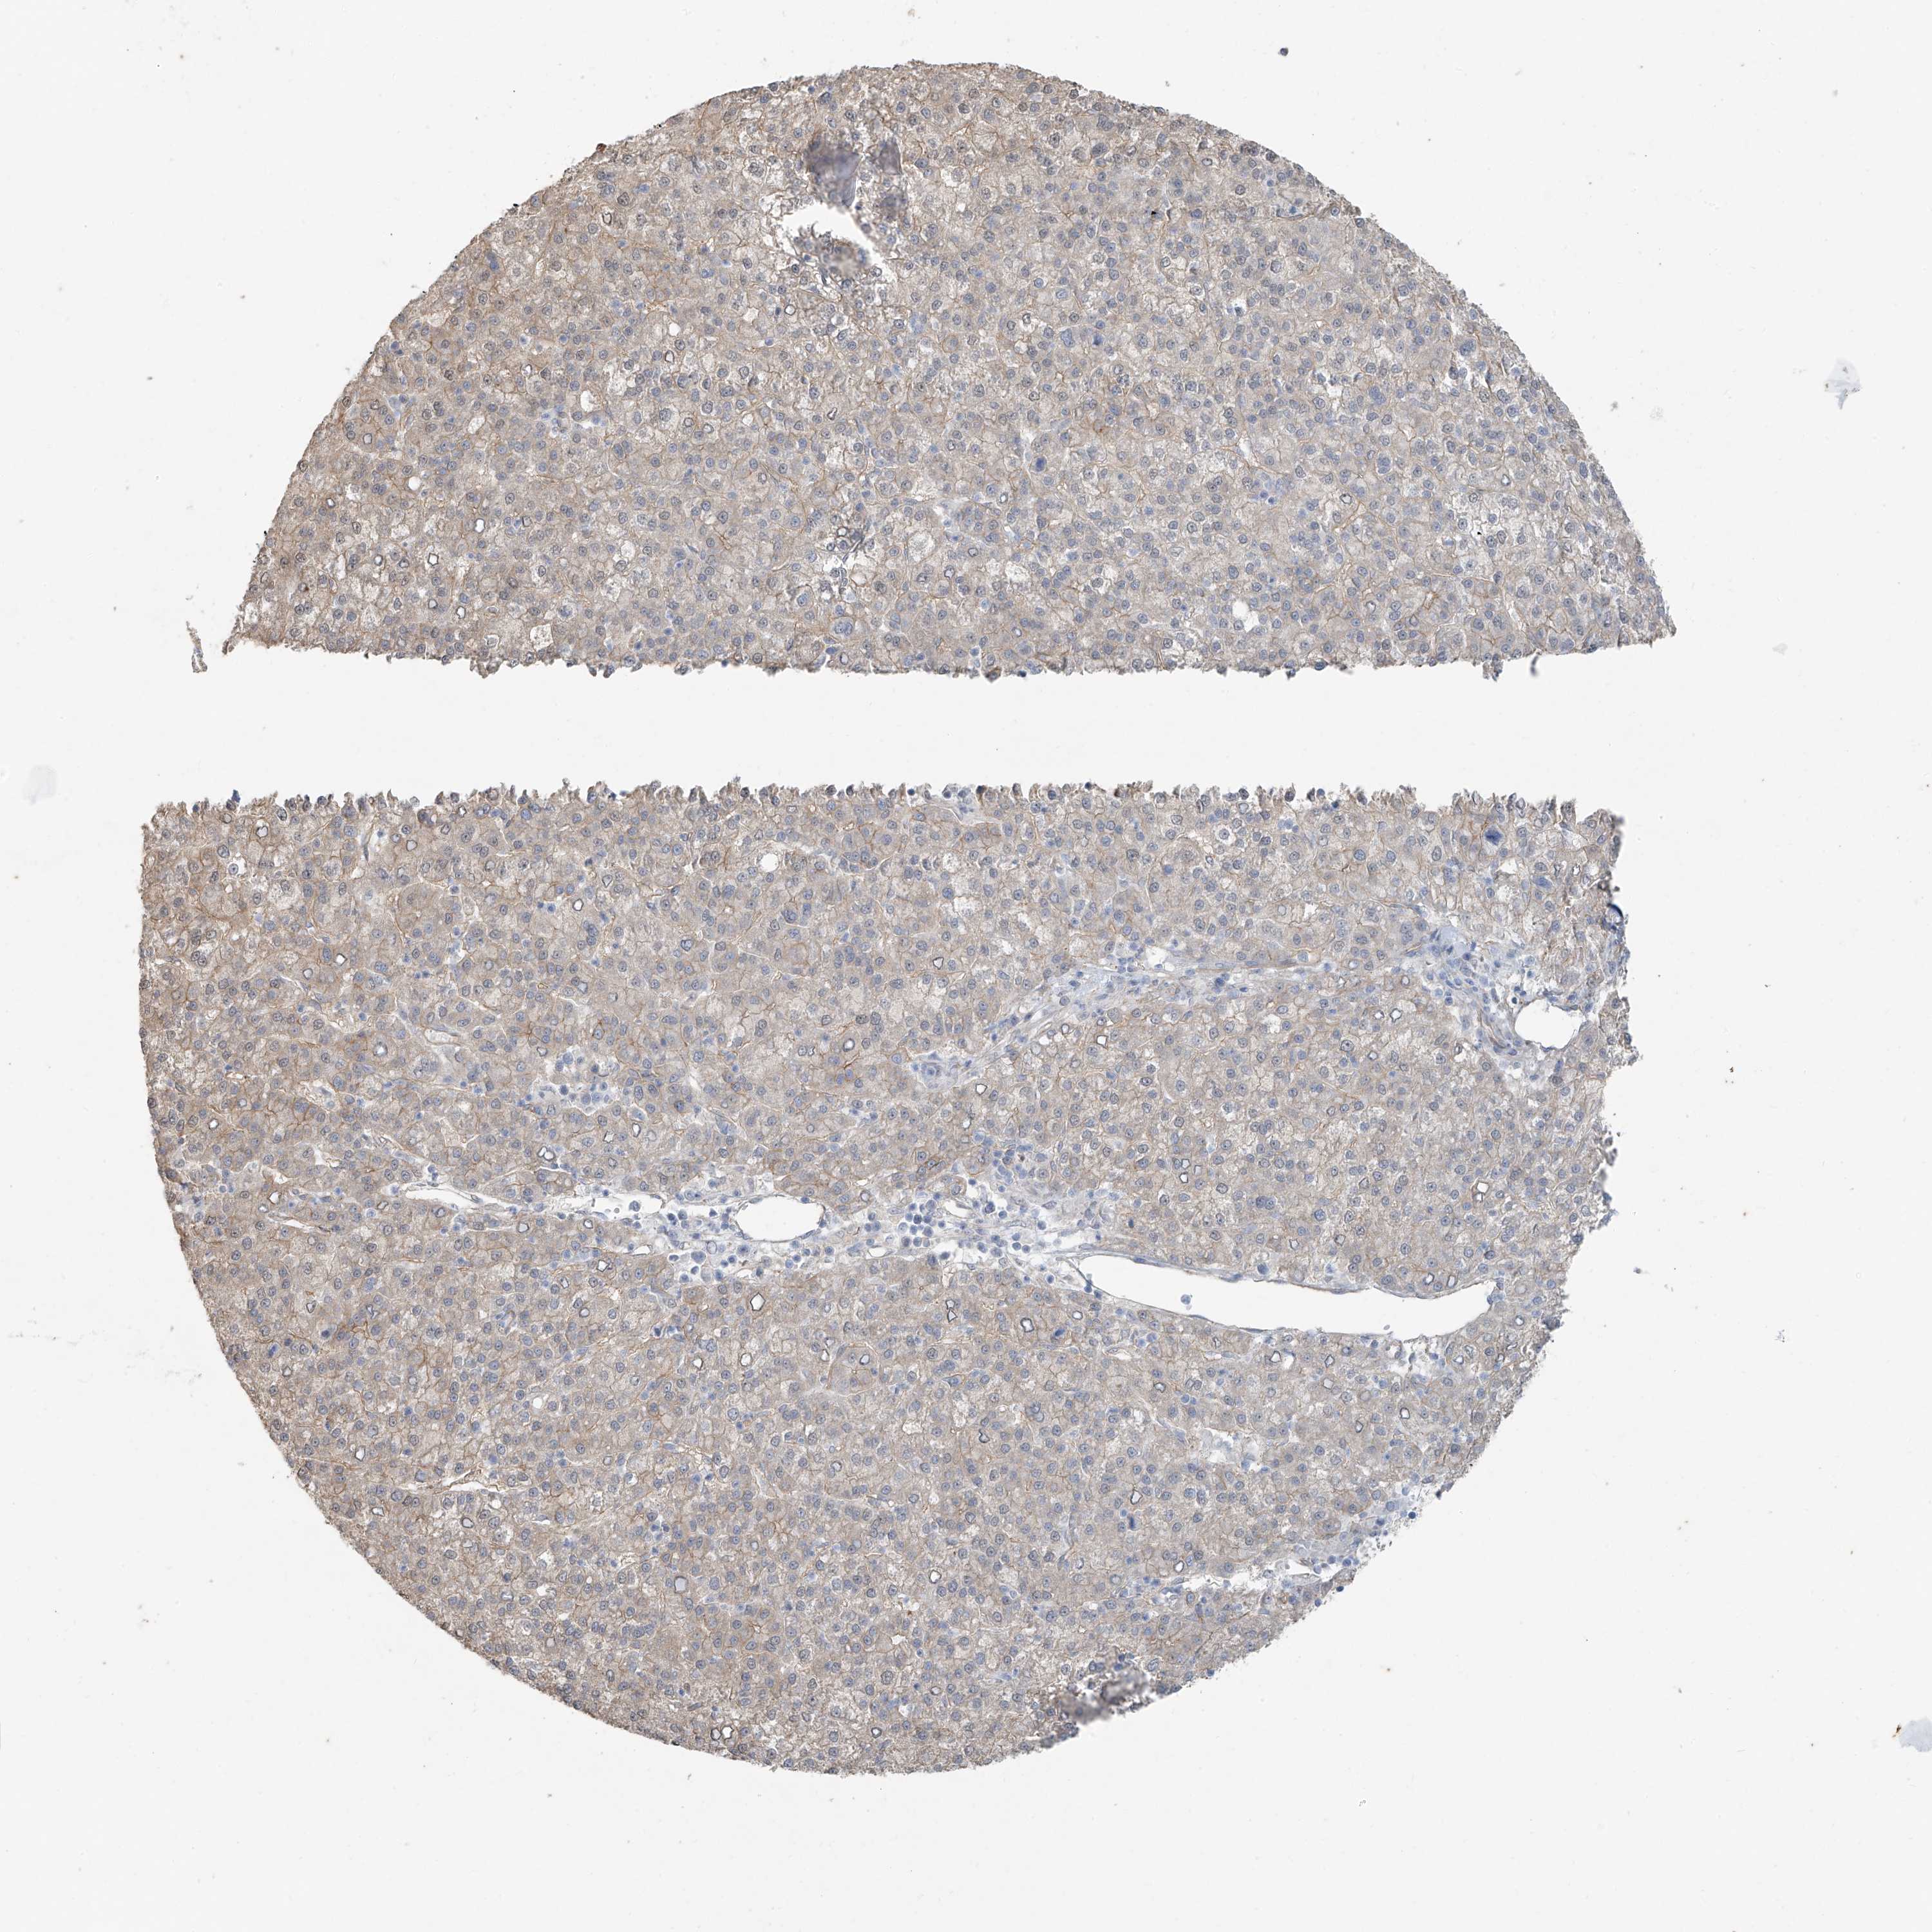

LIVER CANCER - Protein expressioni

A mouse-over function shows sample information and annotation data. Click on an image to view it in a full screen mode. Samples can be filtered based on level of antibody staining by selecting one or several of the following categories: high, medium, low and not detected. The assay and annotation is described here.

Note that samples used for immunohistochemistry by the Human Protein Atlas do not correspond to samples in the TCGA dataset.

Antibody stainingi

Antibody staining in the annotated cell types in the current human tissue is reported as not detected, low, medium, or high, based on conventional immunohistochemistry profiling in selected tissues. This score is based on the combination of the staining intensity and fraction of stained cells.

Each image is clickable and will lead to virtual microscopy that enables deeper exploration of all samples and also displays staining intensity scores, fraction scores and subcellular localization as well as patient and tissue information for each sample.

Antibody HPA032073

Antibody HPA032074

Staining

High

Medium

Low

Not detected

Intensity

Strong

Moderate

Weak

Negative

Quantity

>75%

75%-25%

<25%

None

Location

Nuclear

Cytoplasmic/membranous

Cytoplasmic/membranous,nuclear

Cholangiocarcinoma

Carcinoma, Hepatocellular, NOS